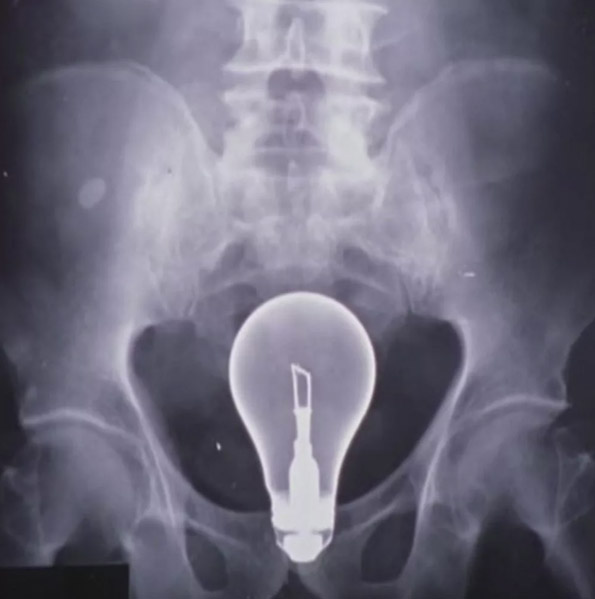

Блин, да как так, шорты, трусы и все равно труба как то попадает точнохонько в цель.

Я начинаю верить в истории от проктологов, когда падают на тюбики и дезики. Страшно.